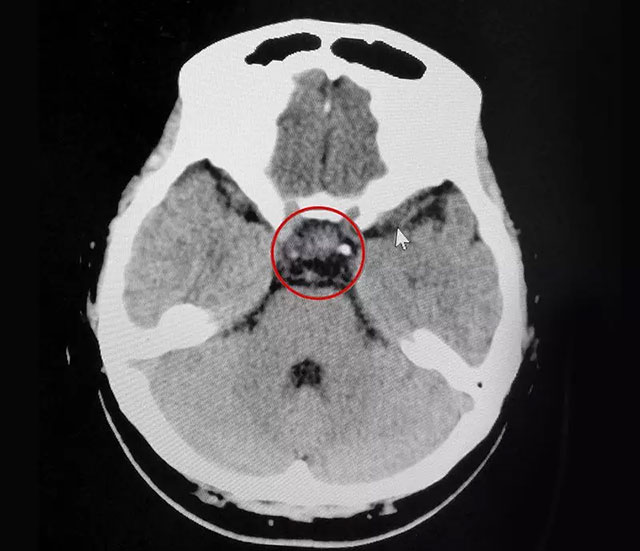

▲ 術(shù)后CT影像顯示:腫瘤切除干凈

“沒(méi)什么感覺(jué),就像打了個(gè)盹。”手術(shù)一周后,劉女士恢復(fù)得不錯(cuò),飲食起居正常,月經(jīng)逐漸恢復(fù)正常,各項(xiàng)內(nèi)分泌指標(biāo)也恢復(fù)正常。目前,劉女士已經(jīng)出院,她將有望圓了自己的“小棉襖”心愿。